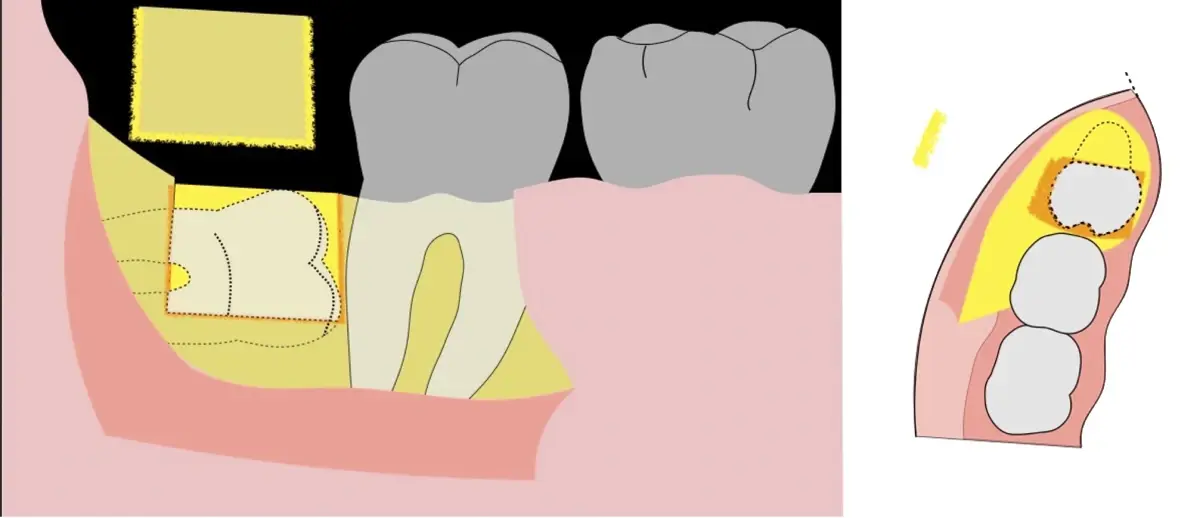

El procedimiento puede variar en su complejidad dependiendo de su ubicación, profundidad, angulación, y la densidad ósea circundante.2 Uno de los pasos más críticos y cruciales en la extracción es la osteotomía previa y concomitante al acceso quirúrgico del diente, para lo cual se utilizan diversos instrumentos como cinceles y martillos, instrumental rotatorio o de corte por ultrasonido.3

El instrumento piezoeléctrico utiliza un corte micrométrico que retira un área de superficie mínima de hueso, y reduce el riesgo de termonecrosis marginal en comparación con las fresas rotatorias convencionales.

En contraste, el instrumento piezoeléctrico utiliza un corte micrométrico que retira un área de superficie mínima de hueso, y reduce el riesgo de termonecrosis marginal en comparación con las fresas rotatorias convencionales.9 Los micromovimientos mejoran la precisión en el corte y el control táctil, y eliminan las macrovibraciones que se producen con los instrumentos rotatorios.10 Su frecuencia de oscilación es la amplitud de 60-200 μm horizontalmente y de 20-60 μm en sentido vertical, lo que es muy inferior en comparación con las micro sierras oscilantes; por lo tanto, proporciona cortes de osteotomía precisos y seguros. Adicionalmente, posee vibraciones ultrasónicas que descomponen el líquido de irrigación en partículas muy pequeñas (fenómeno de cavitación, que produce un efecto hemostático y así reduce la pérdida de sangre), lo que proporciona una visión clara y sin obstáculos del campo quirúrgico11,12.